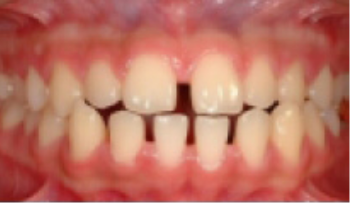

• 총생(Crowding) 치아가 삐뚤게 남.

Before

After